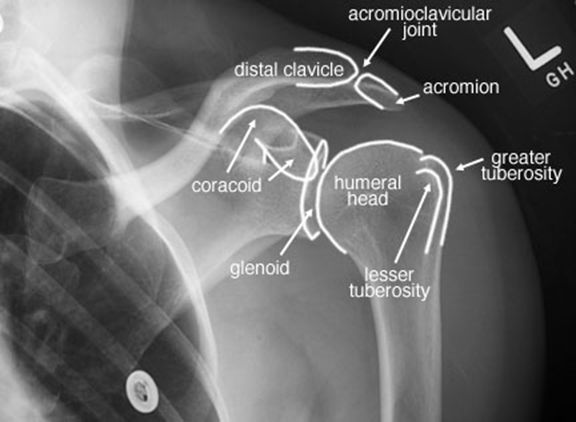

正常肩关节